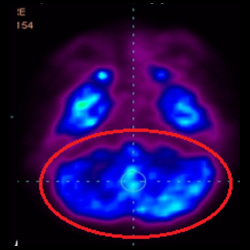

細(xì)胞治療前PET CT掃描顯示神經(jīng)組織中的藍(lán)/黑色區(qū)域,表明腦癱引起的大腦損傷。

細(xì)胞治療后,藍(lán)色和黑色區(qū)域減少,并且看到更活躍的區(qū)域。這表明損傷減少并改善了大腦功能。

細(xì)胞治療前 PET CT 掃描顯示神經(jīng)組織中的藍(lán)/黑色區(qū)域,表明腦癱引起的大腦損傷。

細(xì)胞治療前PET CT 掃描顯示神經(jīng)組織中的藍(lán)/黑色區(qū)域,表明腦癱引起的大腦損傷。

這證明細(xì)胞療法是治療腦癱兒童安全有效的方法。細(xì)胞療法可以更新大腦損傷的核心,并且可以通過 PET CT 掃描來(lái)監(jiān)測(cè)大腦的改善情況。這些細(xì)胞療法與標(biāo)準(zhǔn)治療一起促進(jìn)腦癱兒童的生長(zhǎng)和改善。